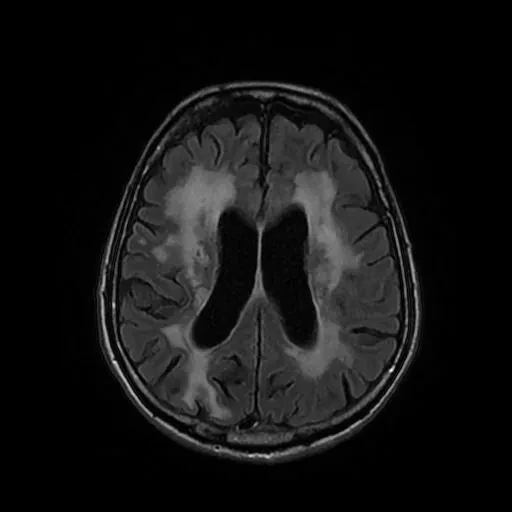

Más allá de la resaca: tres copas al día pueden adelantar 11 años un ictus hemorrágico